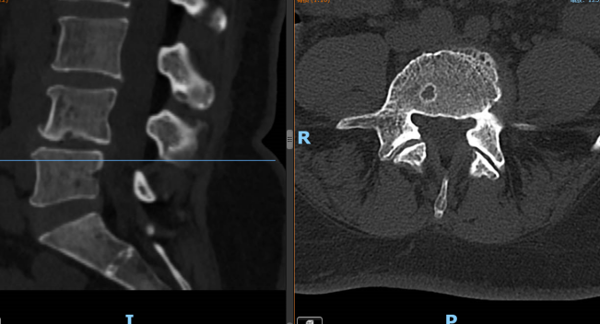

▲③术前CT片

“医生,我这半年来腰痛的厉害,右腿现在又痛又麻,走路都困难,有什么办法处理吗?”在骨科诊室,患者谭阿姨(化名)苦恼地说道。中山一院广西医院骨科脊柱外科专业专家欧裕福副主任医师详细询问谭阿姨病史,并为她安排了细致的检查,最终诊断为腰椎管狭窄症+腰椎滑脱症。

术后第一天,医生为谭阿姨伤口换药并为他进行了腰椎X线及CT复查,显示手术后内固定植入物固定良好,椎间融合器放置在位,下肢麻木及疼痛症状明显好转。经过一系列的康复锻炼,谭阿姨术后第二天下床行走,术后5天办理出院。